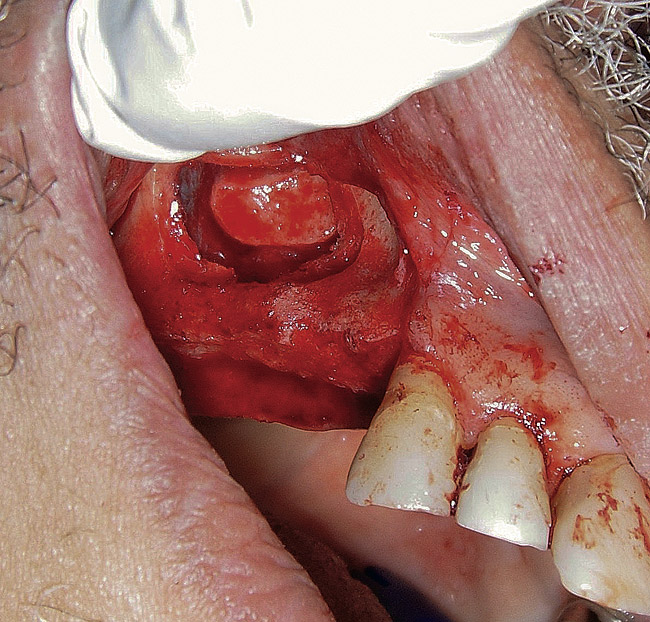

Figure  3   Elevation of the bony window.

Figure 3